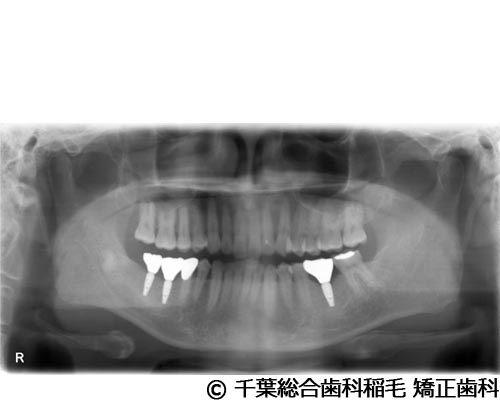

【症例2】下顎大臼歯2本インプラント埋入手術

- 治療前

- 治療後

- 治療名

- 下顎大臼歯2本インプラント埋入手術

- 費用

- 950,000円(税込)

- 期間

- 11ヵ月

治療内容

-

患者様の症状

歯茎の腫れと痛みが主訴でご来院されました。

治療法

右下第一、第二大臼歯は重度の歯周病だったため、保存が難しく、抜歯となりました。

義歯とインプラントそれぞれのメリットデメリットをお話しさせていただき、インプラントでの治療を選択されました。 -

治療結果

お痛みや腫れも和らぎ、現在も定期検診で拝見させていただいています。

※治療結果は患者様によって個人差があります。